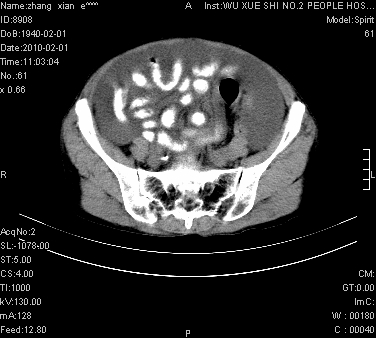

标题: CT24434:70岁 女 腹胀,腹水原因待查 [打印本页]

标题: CT24434:70岁 女 腹胀,腹水原因待查

腹盆腔大量积液,子宫增大,子宫颈增大外形不规则,内见低密度影,膀胱后壁显示不清,右腹股沟肿大淋巴结,脾脏囊性占位,子宫颈占位,子宫颈癌?建议增强。

子宫、宫颈占位?转移性腹水?肝性腹水?脾脏囊性占位,囊肿?血管瘤?淋巴瘤?

考虑:1、腹膜转移,大量腹水;

2、脾占位性病变;

3、左侧卵巢占位性病变,建议增强进一步检查。